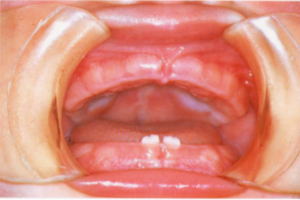

婦人科、母乳外来、おっぱいトラブル、小児歯科 生後6ヶ月から1歳頃に生える上下乳前歯とは?赤ちゃんの虫歯予防2回 前回、健気なエナメル芽細胞についてお話しました。人の体って本当に不思議です。でも泣いてなんか入られません! 可愛い前歯は、下の画像のような形です。 歯が出てきたということは、もっとカロリーを摂る必要が出てきた!という合図でもあります。なぜなら、歯が出てくる時期は、骨格系の成長に合わせるからです。月齢が少なくても、大... 2015年11月13日 しのてぃ